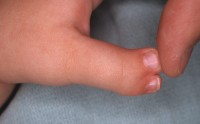

| Case 1. Wassell IV duplication of the proximal and distal phalanges, with characteristic deviation of the thumbs away from each other at the MCP and toward each other at the IP joints. This was corrected by metacarpal head narrowing, opposing closing wedge osteotomies of the metacarpal and proximal phalanx and collateral ligament reconstruction using parts from the deleted digit. |